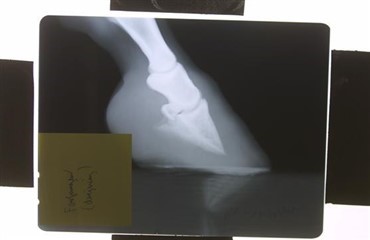

Træsko som led i behandling af forfangenhed. (Foto: Niels Tellerup).

Lidelsen forfangenhed har været vidt diskuteret. Den vigtige afbalancering af hoven er en teknik, som også kan inddrages ved behandling af andre problemer samt forebyggende ved ”raske” heste, f.eks. i handelssammenhæng. En dyrlæge fra Oklahoma viste for få år siden træsko som led i behandling af forfangenhedens akutte fase ved den amerikanske kongres for hestepraktiserende dyrlæger. Det var hans eget koncept. - Vi er gradvist begyndt at bruge dem til de mest forfangne heste, fortæller dyrlæge Niels Tellerup, HesteklinikHerning.dk i sin artikel i magasinet Ridehestens januarnummer. Her kan du læse mere om, hvordan og hvorfor træskoen kan være et yderst vigtigt redskab ud af forfangenheden. Niels har allerede gjort sig gode erfaringer med behandlingsformen på heste herhjemme.